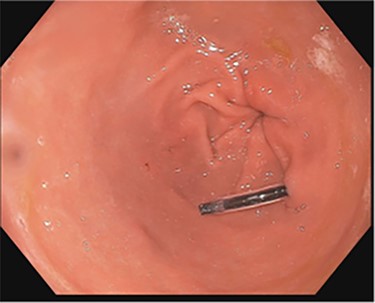

A 43-year-old incarcerated woman with borderline personality disorder and a long history of swallowing various foreign objects in periods of stress presented to the emergency department after swallowing a cup of bleach. Her surgical history was significant for multiple celiotomies for retrievals of purposefully ingested foreign bodies. During evaluation, she also admitted to swallowing an ink pen 3 weeks prior to swallowing the bleach for which she did not seek medical evaluation. She reported no food intolerance or changes in bowel function secondary to swallowing these objects. She presented with mild abdominal pain and cramping, and her vital signs and laboratory investigations were all within normal limits. Her abdominal exam was notable for mild tenderness to palpation diffusely. Computed tomography (CT) of the abdomen (Fig. 4) showed a linear foreign body in the distal gastric antrum penetrating the inferior wall and extending into the adjacent peritoneal fat. No free air or free fluid was appreciated. Initial esophagogastroduodenoscopy (EGD) was significant for mild erythema and edema to the esophageal and duodenal mucosa as a result of the caustic ingestion, and the pen was found to be deeply perforating the stomach antral wall with no associated ulcer or edema (Fig. 1). The depth at which the foreign body was lodged was uncertain, so there was concern for organ involvement outside of the gastric wall. Repeat EGD was done to assess for manifestations of esophageal, gastric or duodenal injuries from her caustic ingestion, and it revealed normal gastric mucosa (Fig. 2). A joint case was planned with the gastroenterology service for endoscopic foreign body retrieval, possible laparoscopic retrieval and gastric repair and possible open retrieval and gastric repair. The patient was taken to the operating room for the third EGD, which revealed spontaneous migration of the foreign body from the perforation site into the lumen of the gastric body (Fig. 3a). Additionally, there was spontaneous closure of the site of previous perforation (Fig. 3b and c). The ink pen was easily removed transorally using an endoscopic snare, and no further surgical intervention was required. After the procedure, the patient reported complete resolution of her abdominal pain and was able to tolerate a regular diet without problems.

(a–d) Subsequent EGD 1 week later; (a) foreign body in the fundus of the stomach; (b and c) irregularity in the antrum corresponding to site of previous perforation; (d) ink pen after transoral endoscopic removal.